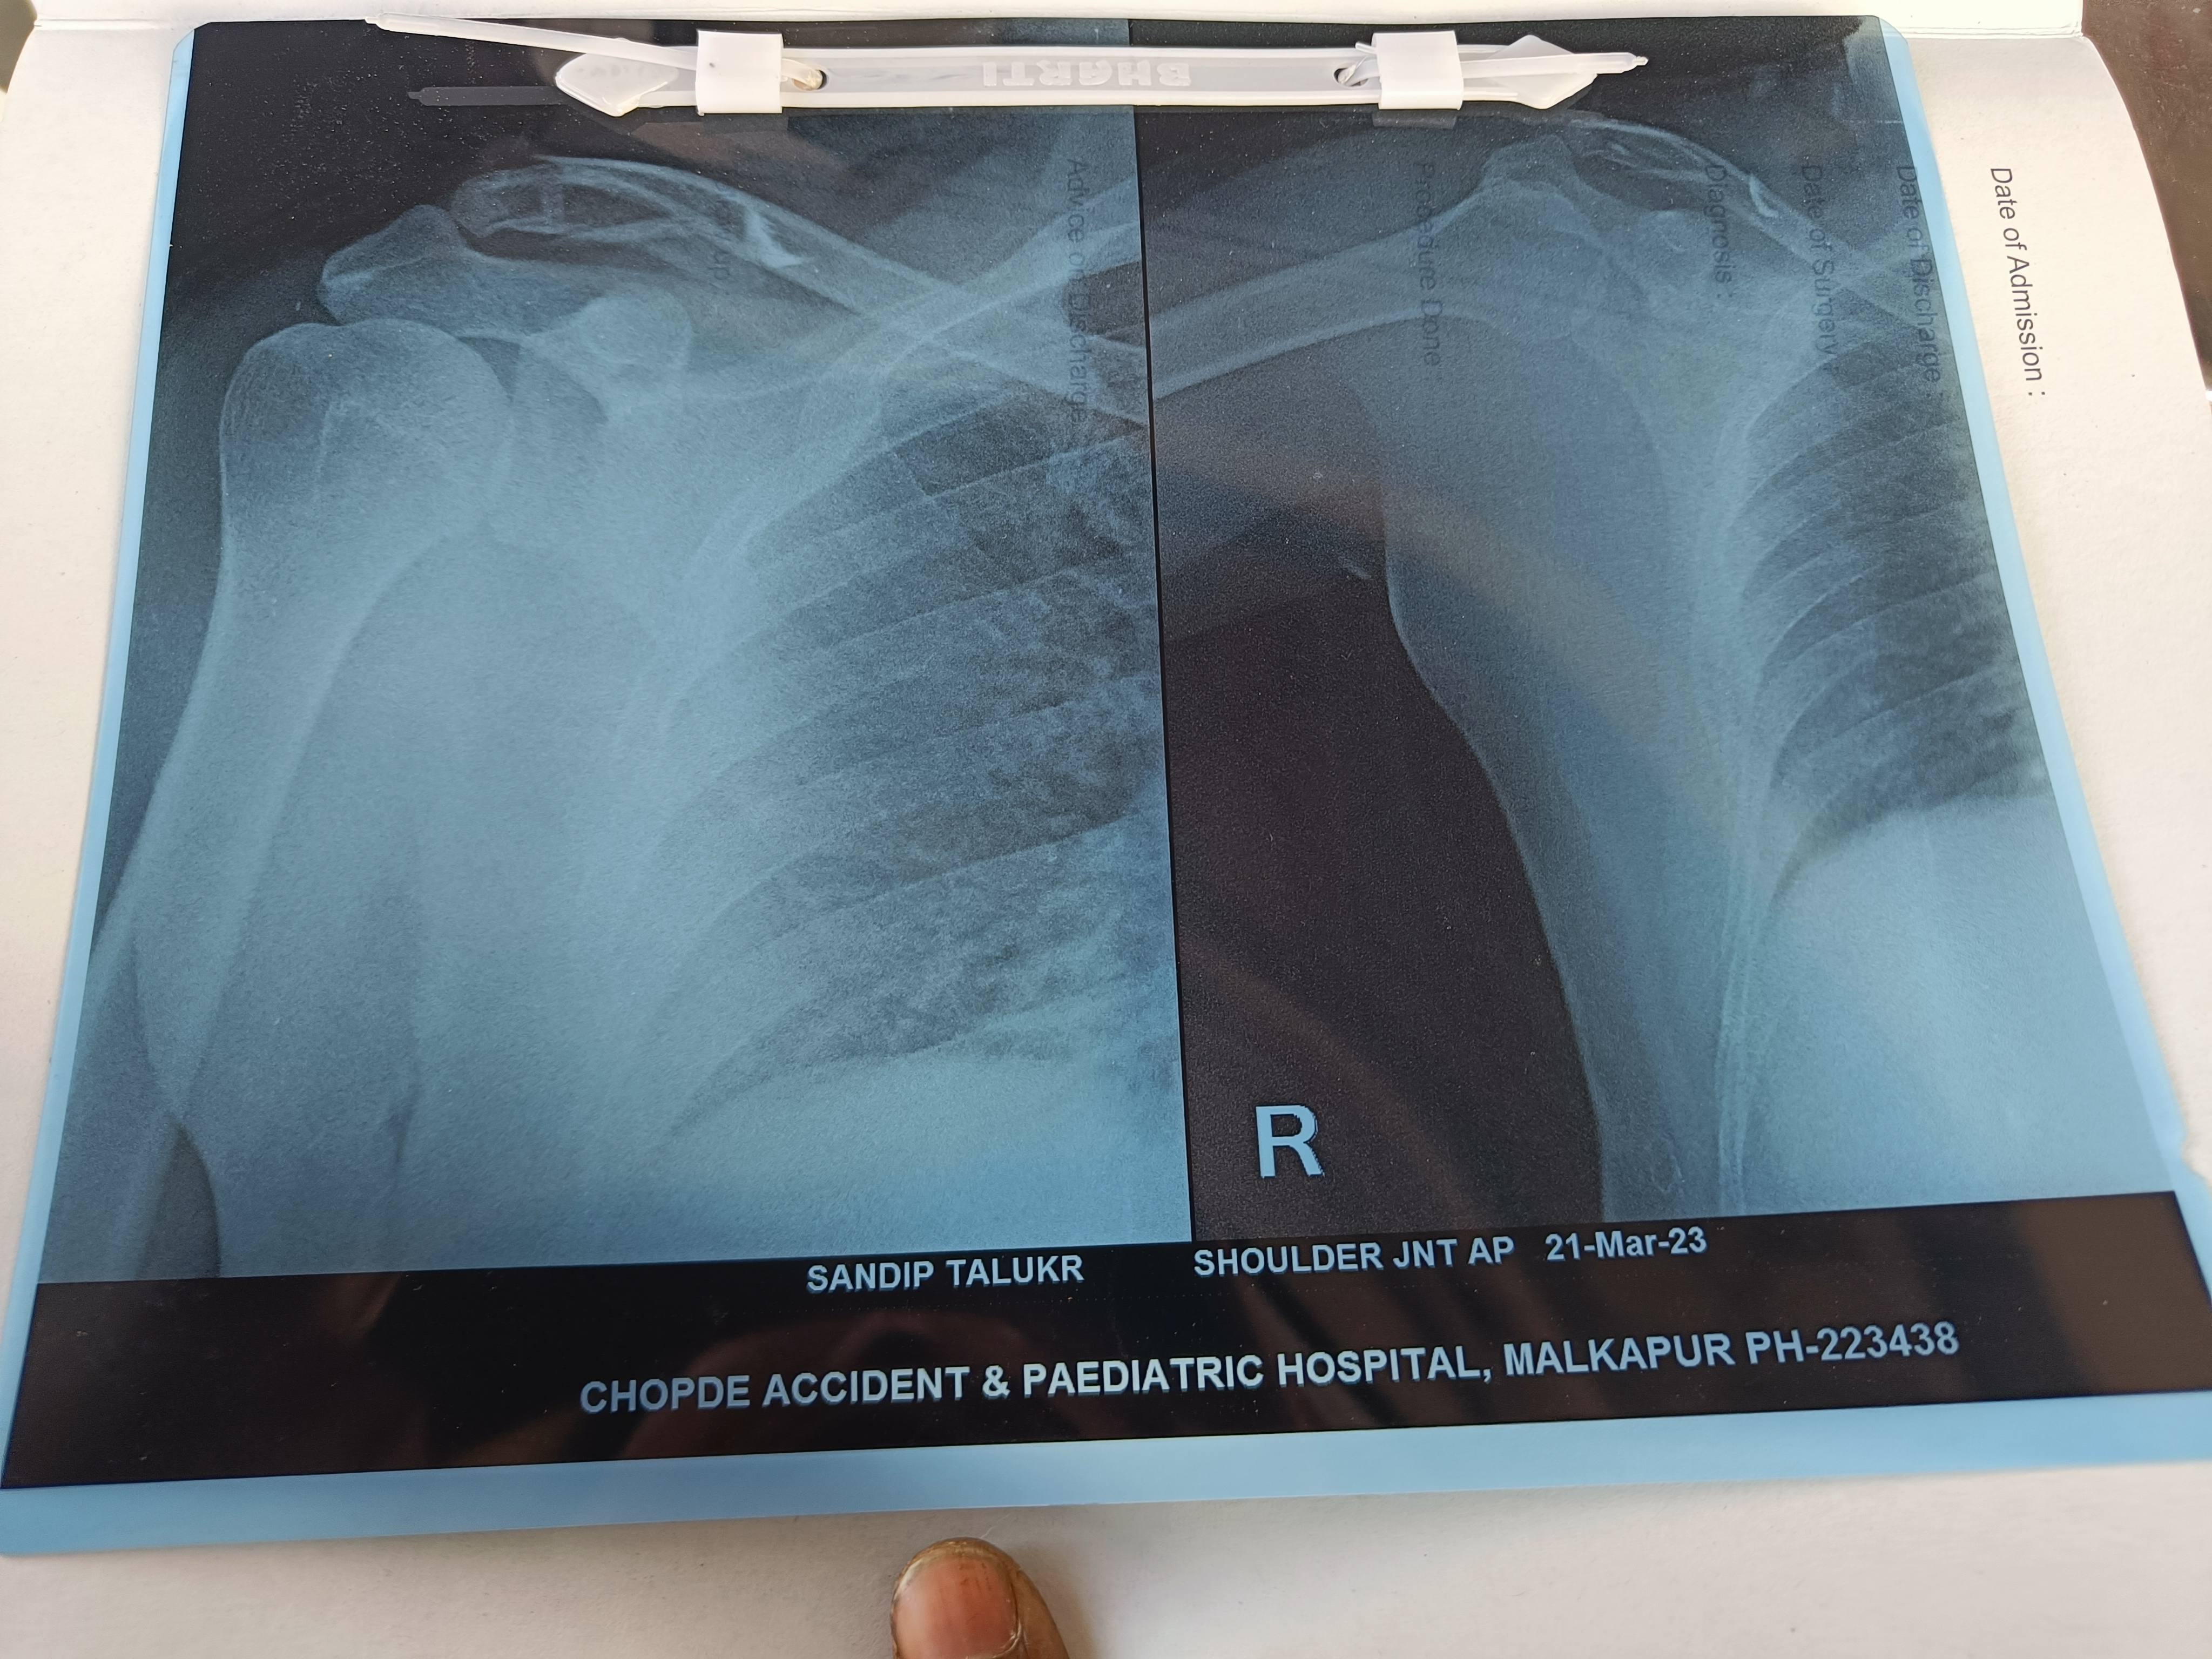

SANDIP TARUKAR

Sir mera clavical facture he